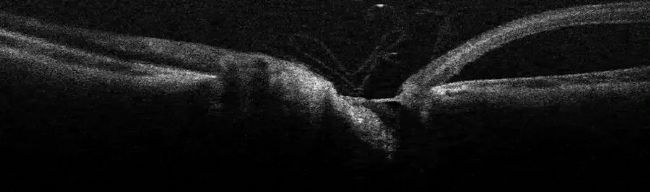

在這個視網膜脫離病例中,眼窩和黃斑脫落。由于視網膜的鏡像效果(圖 7),術中 OCT 幫助評估了視網膜脫離的程度。因此,視網膜脫離可以在手術室內記錄下來。

圖 7:術中 OCT 圖像顯示視網膜鏡像,右側是脫落的眼窩。圖片由 Nikolaos Bechrakis 教授提供。